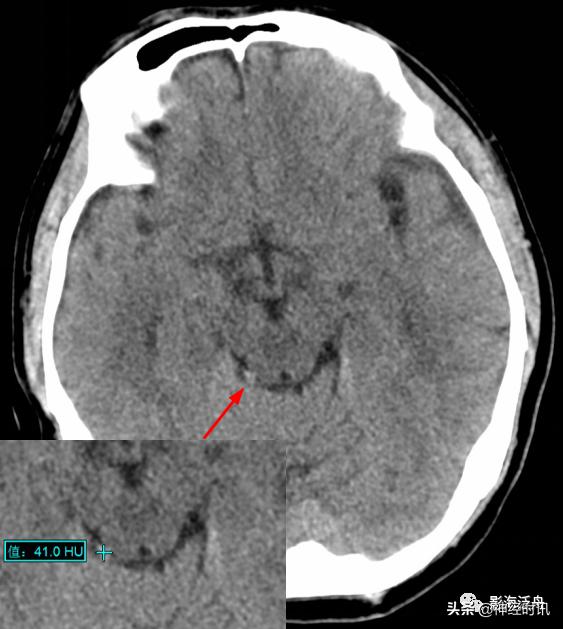

高空坠落伤患者,外伤后不到2h行头颅CT检查,整个片子中只有右侧环池可见斑片状高密度影,CT值57HU,36小时后复查,病灶密度减低,CT值约41HU,本例为少量蛛血的典型病例。

由于脑脊液的流动冲刷作用,蛛网膜下腔少量出血所形成的小血肿远没有脑实质内的血肿稳定,即便在外伤后第一个24h内,其CT值也很难超过60HU(课本上讲的脑内血肿极限CT值为94HU,平时工作中当然不可能遇到,但70+HU的血肿还是很常见的)。所以诊断少量蛛血的最佳时间是在外伤后第一个24h内,一旦超过24小时其CT值就会快速衰减,3天以后基本上很难在CT平扫上看到高密度影。